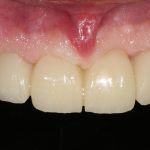

Наверное, 45-летний мужчина будет жаловаться на то, что внешность изменилась, ни разговаривать, ни улыбаться невозможно, девчонки его не любят, а он только что женился/развелся, у него только жизнь начинается, а тут такое… И, как мне кажется, он ожидает, что стоматолог ему сделает зубы даже лучше тех, что у него были, по всем параметрам.

Что мы ему предложим? Разумеется, несъемное протезирование с опорой на 6-8 имплантатов:

Это в большей степени будет удовлетворять его пожеланиям и требованиям. Фактически, он получит новые зубы, только искусственные: